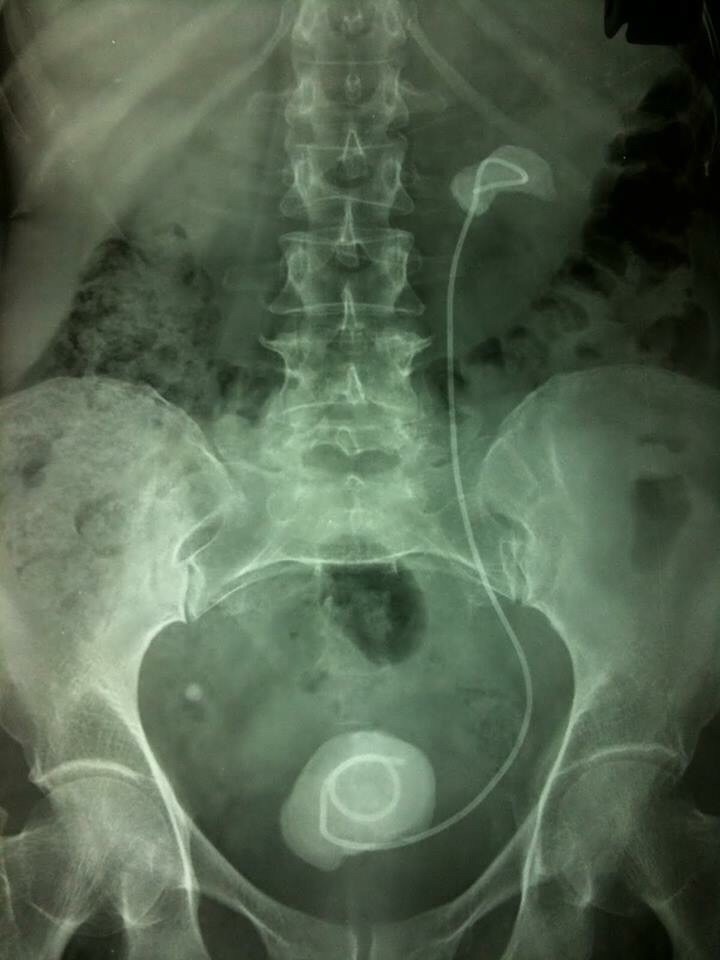

Diagnosis

Diagnosis of stone is mainly radiological with ultrasound and x-rays. Laboratory Tests are performed to look for urine infection and function of the kidneys:

• • X Ray abdomen and pelvis

• • Ultrasound KUB

• • IVU (Intravenous Urography)

• • CT Urography